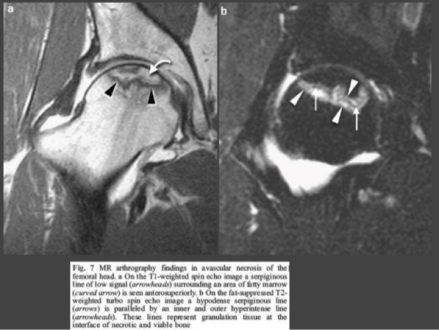

Imaging

- Magnetic Resonance Imaging